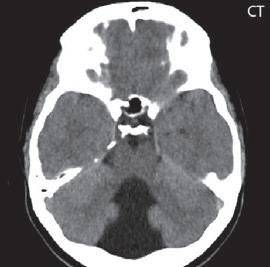

I.1.8 Dandy-Walkerova malformace (D-W variant, D-W komplex, D-W spektrum )

Zobrazení

D-W malformace je charakterizována hypoplazií vermis mozečku, rozšířením IV. mozkové komory, která se často cysticky vyklenuje dorzálně a může imitovat arachnoidální cystu, rozšířením zadní jámy lební a vysokým úponem tentoria s confluens sinum nad lambdovým švem. Okcipitální kost může být vlivem tlakových změn remodelována, existují i případy s porušením její kontinuity a encefalokélou. Hydrocefalus pozorujeme v 80 %, častá je přítomnost dysgeneze corpus callosum, schizencefalie.

D-W variant byl vyčleněn pro případy, kdy všechny základní příznaky nemusí být plně vyjádřeny nebo může některý zcela chybět. Bývá přítomna hypoplazie mozečku, což je dominantní příznak, IV. komora je obvykle rozšířena, někdy pozorujeme, že tvarem připomíná na axiální řezu „klíčovou dírku“, zadní jáma lební naopak rozšířena nebývá.

Obr. I.1.8a Dandy-Walkerova malformace, rozšířená IV komora (tvar klíčové dírky)

Obr. I.1.8b Dandy-Walkerova malformace, rozšířená IV komora široce komunikující s cisterna magna, hypotrofie mozečku (snímky zapůjčeny z archivu prim doc MUDr M Mechla, Ph D, MBA)

Obr. I.1.8c Dandy-Walkerova malformace, rozšířená IV komora široce komunikující s cisterna magna, hypotrofie mozečku (snímky zapůjčeny z archivu prim doc MUDr M Mechla, Ph D, MBA); stejný pacient jako na obr I 1 8b

Obr. I.1.8d Dandy-Walkerova malformace, rozšířená IV komora široce komunikující s cisterna magna, hypotrofie mozečku, vysoký úpon tentoria (šipka) (snímky zapůjčeny z archivu prim doc MUDr M Mechla, Ph D, MBA); stejný pacient jako na obr I 1 8b, c